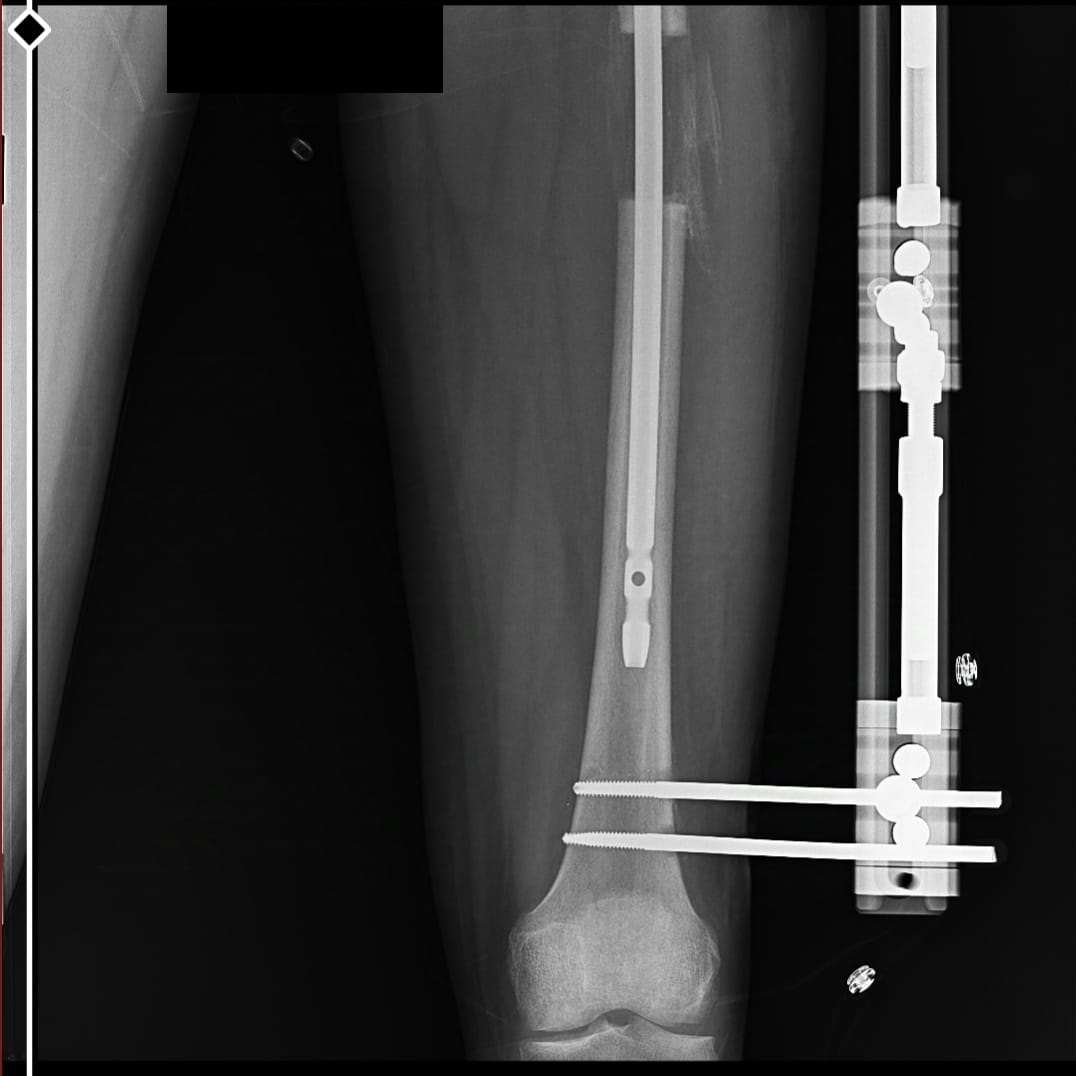

these are just before removing external fixatorAttachments:

This is my after fixator removal xray00 -